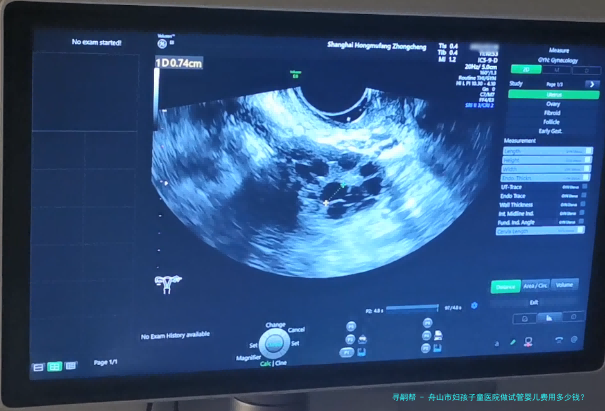

希望拥有本人的宝宝,但因为诸多原因无从自然受孕,试管婴儿就成为无数家庭的曙光。舟山市作为一个享有许多优质医疗机构之处,也提供着完备的试管婴儿服务。哪样舟山市妇孩子童医院做试管婴儿费用多少钱?成功率怎样呢?

以下我们将给您详细介绍舟山市妇孩子童医院的试管婴儿相关信息,盼望能解答您心中的纳闷。